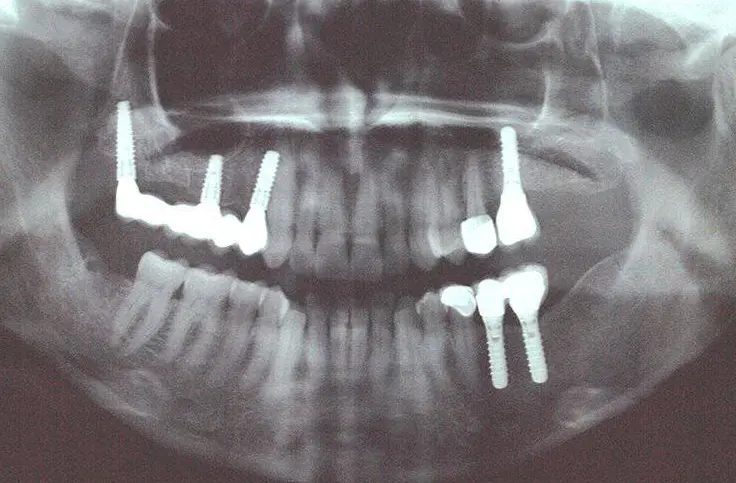

Cuando la pérdida ósea es tan severa que ni siquiera permite colocar un implante convencional, existen técnicas de implantología avanzada que sortean ese problema. En lugar de intentar colocar el implante donde ya no hay hueso, lo anclamos en zonas del cráneo que mantienen su densidad con el tiempo.

Se anclan en el hueso del pómulo. Para casos de pérdida severa en el maxilar superior. Evitan injertos largos. Más información sobre los implantes cigomáticos y cuándo están indicados.

Se anclan en el hueso pterigoideo, en la zona posterior del maxilar superior. Son ideales cuando la pérdida ósea es mayor en la parte trasera del paladar. Se combinan con otros implantes para rehabilitar toda la arcada superior.

Son tornillos de titanio de diámetro reducido (aproximadamente 2 mm), diseñados para casos en los que el hueso disponible no es suficiente para un implante convencional pero sí permite anclar uno más pequeño. Son una solución excelente para estabilizar dentaduras y para zonas con hueso estrecho.